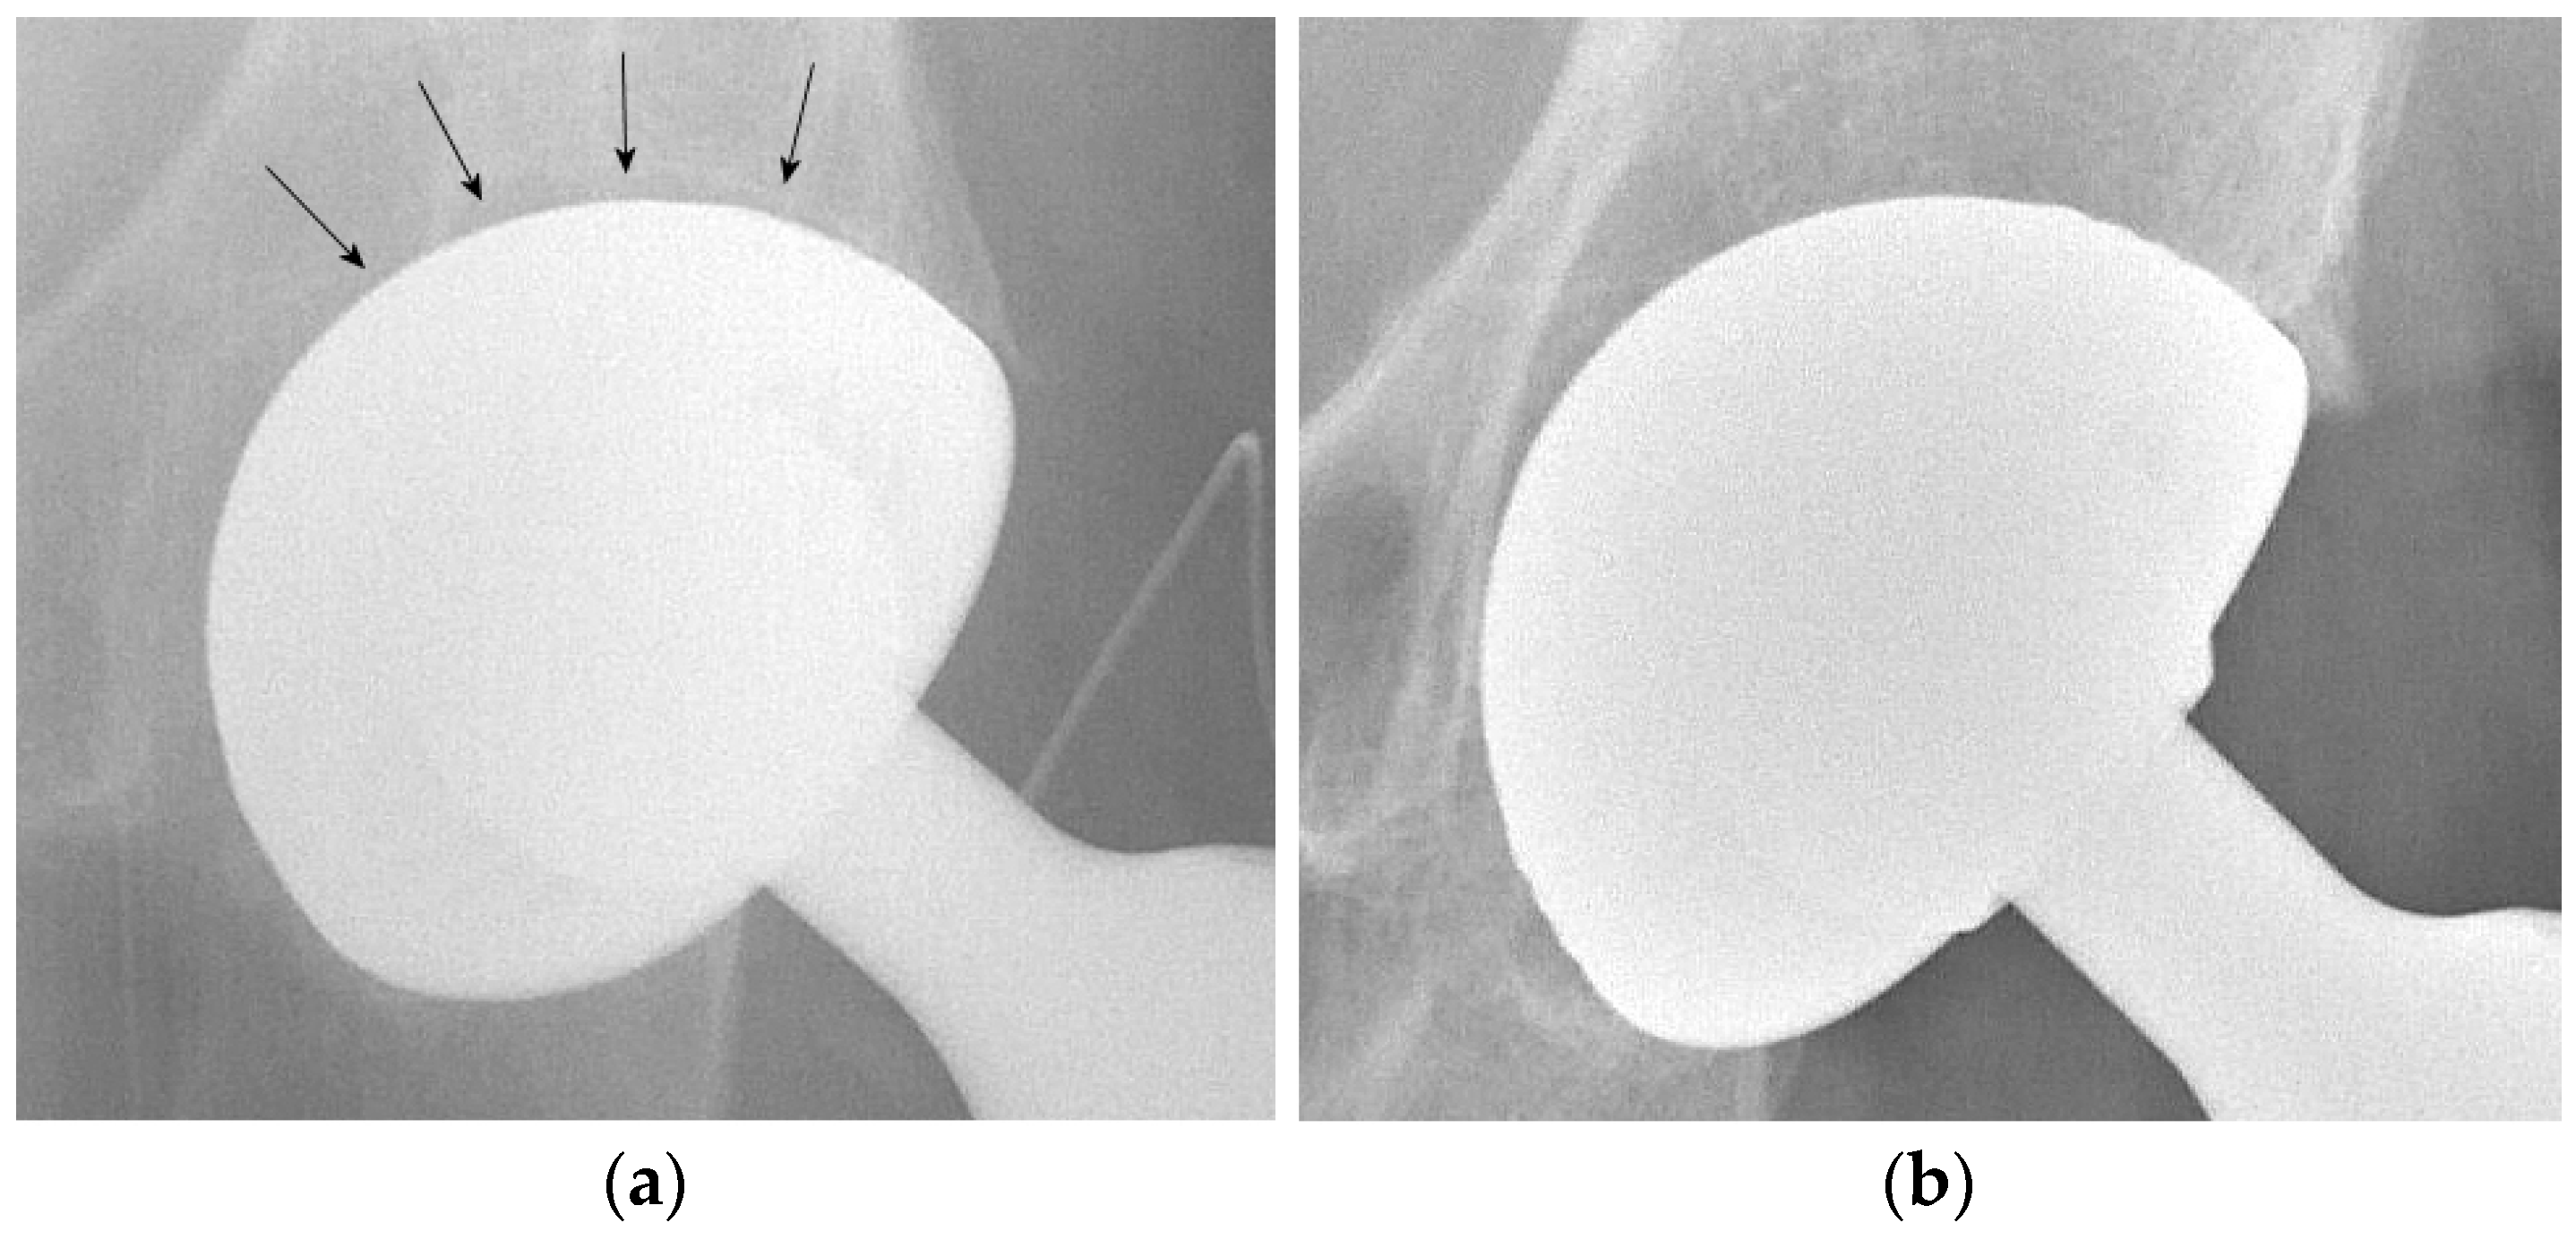

No dislocation occurred in the DMC group, while two dislocations were observed in the SC group. Both dislocations occurred during the first month after surgery: one in a male patient following an accidental fall and one in a female patient without any traumatic event. The first patient was treated with closed reduction and THA dislocation never recurred. The female patient suffered of postoperative moderate-grade delirium with poor cooperation in the rehabilitation program; dislocation occurred twice in the rehabilitation institute. In consideration of her mental state and poor compliance, she underwent a revision procedure: the femoral stem and acetabular cup were retained, the liner and the head were substituted and a neck adapter (Bioball®, Merete GmbH, Berlin, Germany) was implanted to increase length and lateral offset in order to enhance implant stability (Figure 1). Dislocation did not recur and at follow up the patient reported complete recovery of autonomy and preoperative activities.

Figure 1. (a) Displaced intracapsular fracture (Garden-type IV) of the right femoral neck in a 79-year-old woman. (b) Postoperative radiograph after surgical treatment with a conventional THA. (c) Prosthesis dislocation 3 weeks after surgery. (d) Radiograph after implantation of a neck adaptor to increase length and lateral offset.